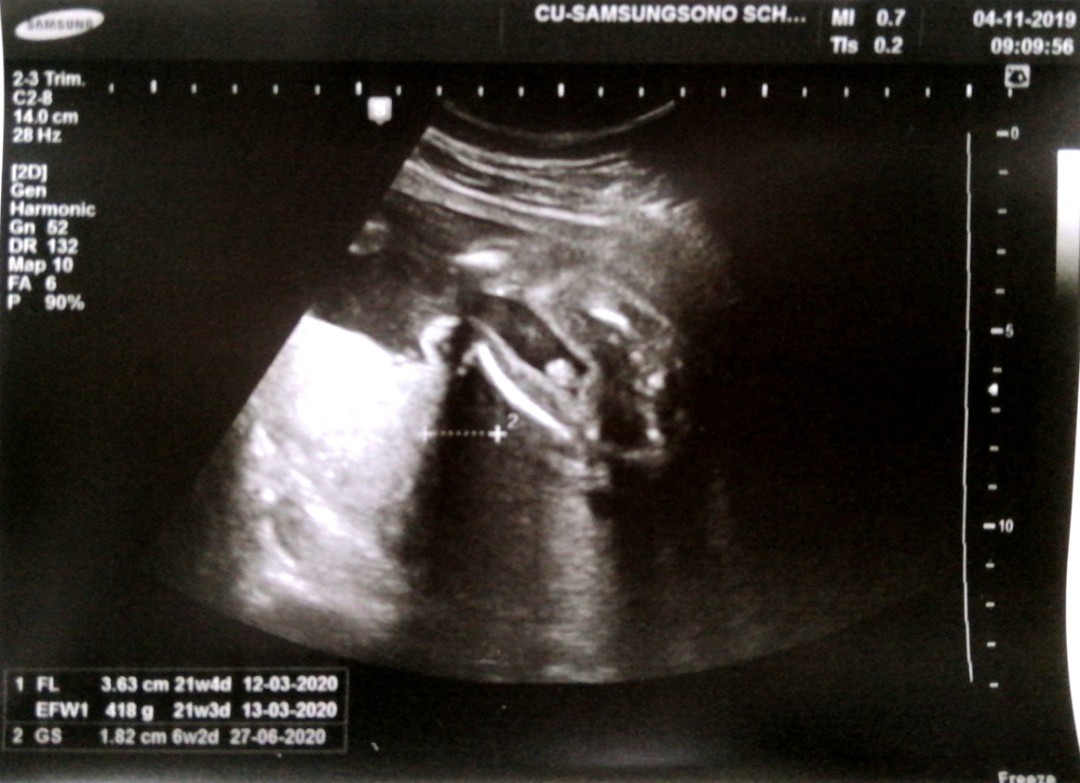

กำหนดคลอดเดือนมีนา63

บ้านไหนกำหนดคลอดเดือนมีนาคม63บ้างค่ะ บ้านนี้10มีนาคม63 ยังไม่รู้เพศ หมอไม่ดูเพศให้ค่ะ

บ้านนี้กำหนดคลอด21มีนาคะ ยังไม่รุ้เพศเหมือนกันคะ

บ้านนี้3มีนาจ้า หมอบอกว่าน่าจะเพศชายจ้า

30 มี.ค ครับ. หมอบอก ผญ 80% ผช20% ทักทายแม่ๆๆครับ

ลุ้น25นี้ครับ. หมอบอหไม่แน่นอาจ ผช. ครับ.

10 มีนา เหมือนกันเลยค่ะ ผญ รู้เพศตั้งแต่ 15 w

10มีนาเหมือนกันจ้า ได้ลูกชายจ้าบ้านนี้

กำหนด11มีนาคมค่ะ ยังไม่รู้เพศเลย

8มีนาค่ะหมอบอกน่าจะ ผญ น้องหนีบๆขาไว้

10 มีนา ผช ค่ะ ซาวด์ครั้งก่อนเห็นชัดเลย